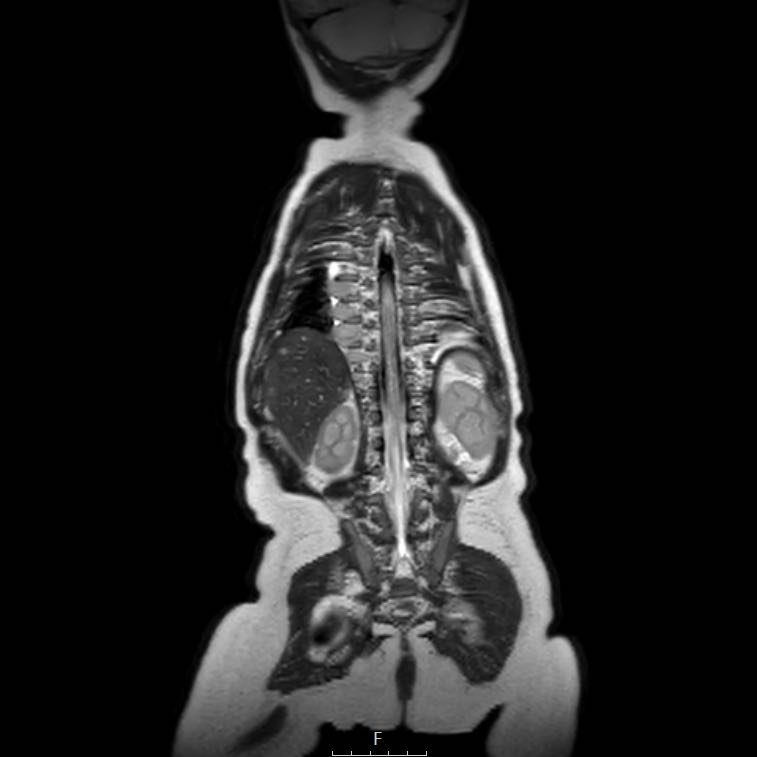

Cuộn qua chuỗi ảnh T2 theo mặt phẳng coronal.

Nghiên cứu các hình ảnh và sau đó tiếp tục đọc.

The findings are:

- Mass with encasement of the aorta and splanchnic vessels.

- Lan rộng dọc theo cột sống ngực nhưng không xâm lấn vào ống sống.

- Small liver metastases.

- Left supraclavicular mass.

Same patient.

Mức độ lan rộng của khối u được đánh giá rõ ràng trên chuỗi xung TSE T2 weighted 3D theo mặt phẳng axial.

The left kidney is compressed and displaced caudally.

Có di căn hạch bạch huyết cạnh động mạch chủ (mũi tên vàng nhỏ).

Nguyên ủy của thân tạng và động mạch mạc treo tràng trên bị khối u bao quanh (đầu mũi tên).

Tĩnh mạch chủ dưới bị đẩy ra phía trước (mũi tên xanh).

Xẹp phổi hai bên ở vùng lưng thường được thấy trên MRI, vì việc kiểm tra được thực hiện dưới gây mê.